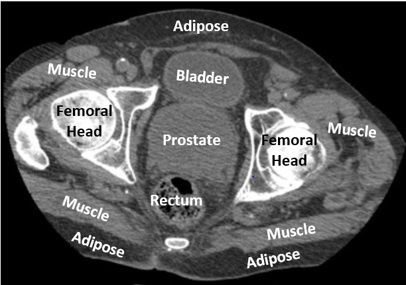

A scanned image of a patient's pelvis. Photo/Range Assure.

(Photo 1) CT imaging of the pelvis is reflected in Range Assure's human-like phantom model, which replicates the patient's anatomy. Photo/Range Assure

Traditional calibration phantoms are typically smooth, oval-shaped, and made of uniform materials, failing to reflect the complexity of the human body. By contrast, Range Assure’s solution is designed to mimic the human male pelvis, closely mirroring how radiation interacts within real bodies and supporting more confident treatment planning.

Range Assure shapes its phantom models using multiple methods, including CT imaging (Photo 1). Inside the clear disc, the white cylindrical material, or TEMs, is accurately arranged to mimic the tissue composition and anatomical dimensions of organs in the pelvis. Photo/Range Assure

This lifelike matching of organ makeup, shape, and layout lets you see how Range Assure’s phantom empowers clinicians to predict with greater confidence where proton radiation will stop in the body.